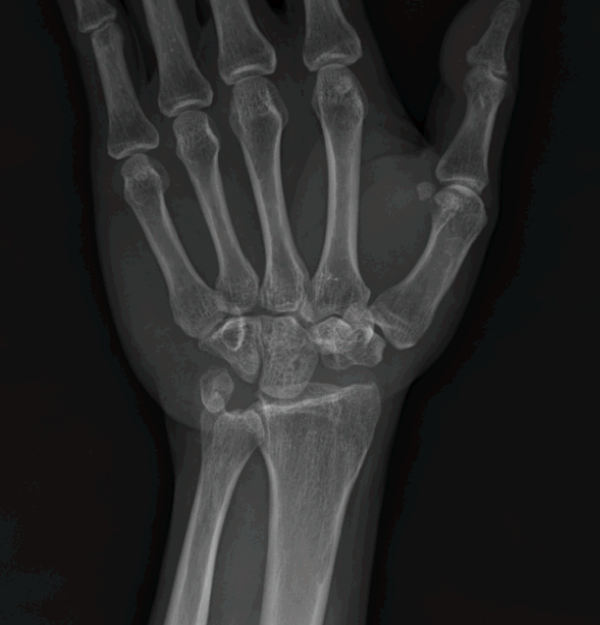

주상월상인대파열

손목 뼈 사이에는 뼈들을 연결하는 내재인대들이 존재하는데, 그 중에서 주상골과 월상골을 연결해주는 인대를 주상월상인대라고 합니다.

주상골과 월상골 사이의 관절면은 서로 협동적으로 움직이는데 여러가지 원인으로 인대 파열되는 질환을 주상월상인대파열이라고 합니다.

주상월상인대파열 진단법

X-ray 진단으로 보이지 않을 경우

→ 초음파, MRI 영상 검사

주상골, 월상골 사이 인대는 아주 작아 MRI 로 진단이 어려운 경우

→ 손목관절 내시경을 통해 진단

힘주지 않았을 때 우측

힘주지 않았을 때 좌측